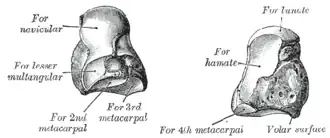

Le capitatum est constituée d'une tête arrondie en haut et d'un corps en bas, reliés par un col rétréci.

Il présente six faces :

- une face supérieure ronde et lisse qui s'articule avec le lunatum,

- une face inférieure divisée par deux crêtes en trois facettes articulaires pour la base des deuxième, troisième et quatrième métacarpien,

- une face latérale possédant une petite surface articulaire antéro-inférieure pour le trapézoïde, au-dessus le sillon du col forme une dépression rugueuse pour l'insertion d'un ligament interosseux et au-dessus de celui-ci une surface articulaire lisse et convexe pour le scaphoïde,

- une face médiale avec une facette articulaire postéro-supérieure pour l'hamatum et à l'avant une surface rugueuse d'insertion d'un ligament interosseux.